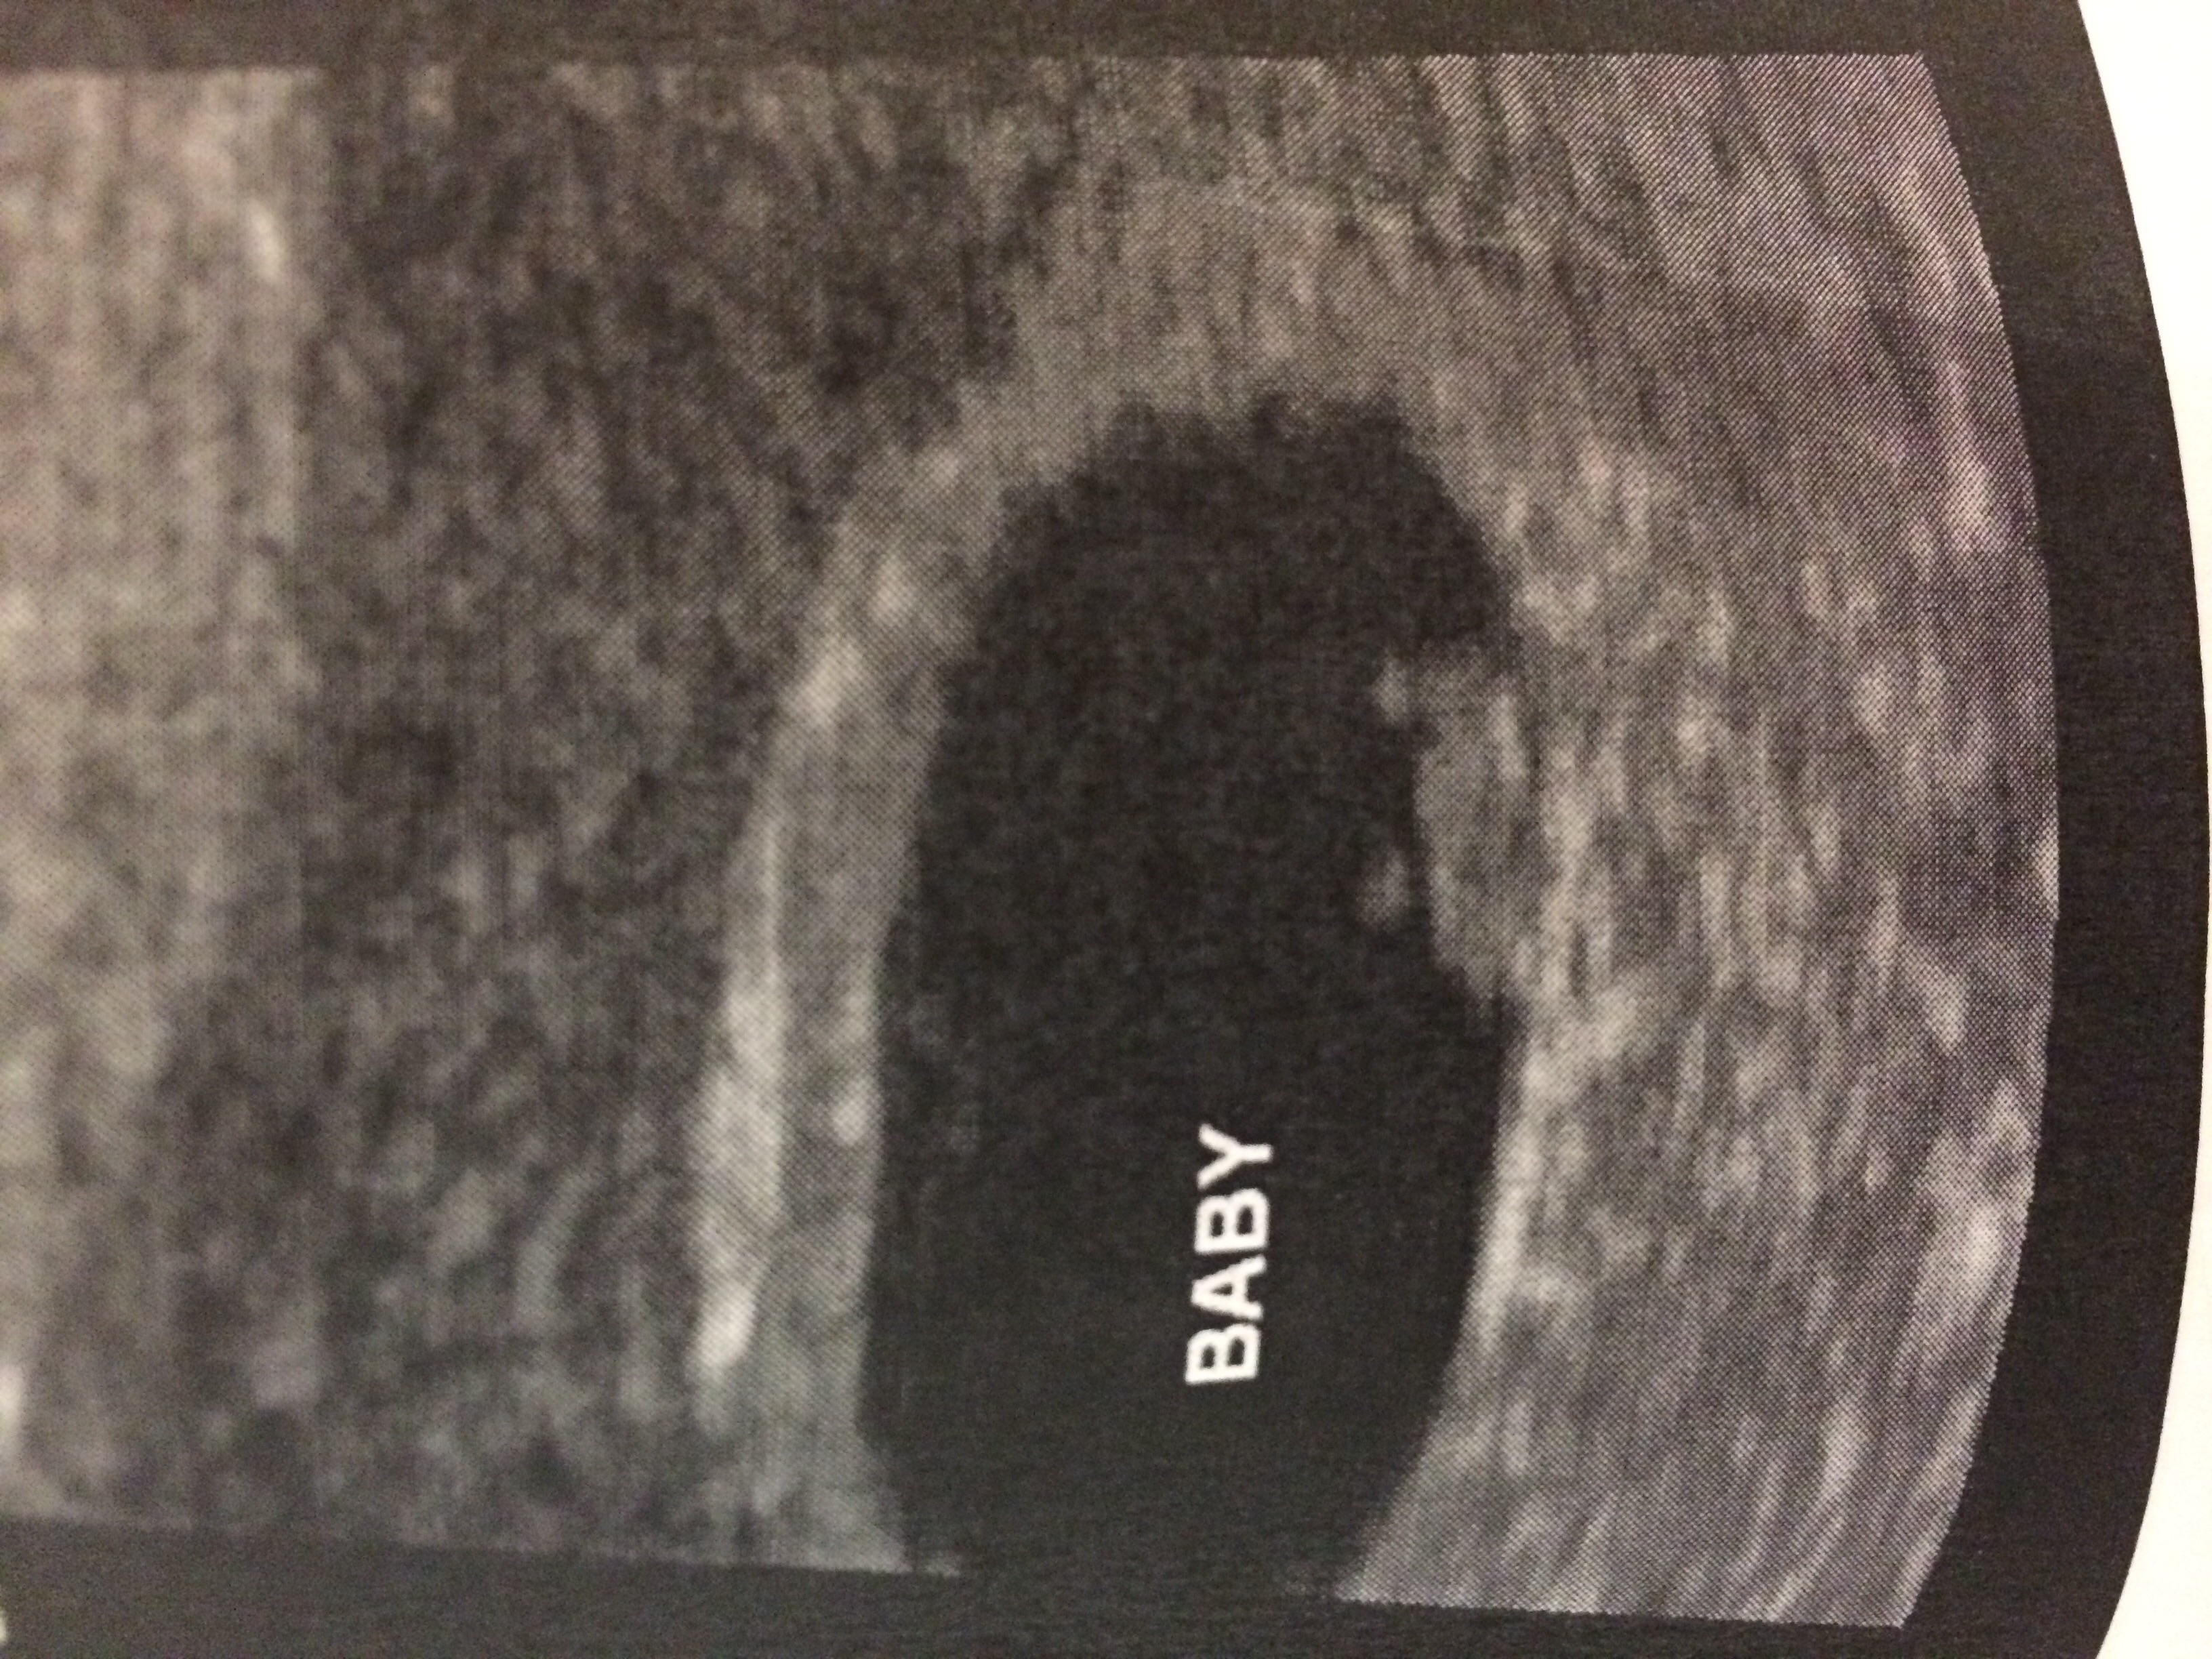

This is transvaginal at 10w2d

The thick white area to the bottom left seems to be the start of the placenta, so it looks just like the first picture in @adcc43 's example, so boy.